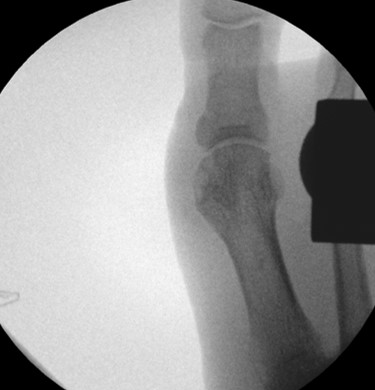

• Notwendigkeit der intraoperativen Bildvestärkerdiagnostik.

• Röntgenaufnahme des Fußes (unter Belastung) in dorsoplantarem und seitlichen Strahlengang (Abb. 3) und präoperative Fotodokumentation.

• Beurteilung des proximalen Gelenkflächenwinkels der Grundphalanx (Proximal Phalangeal Articular Angle, PPAA) des Hallux valgus interphalangeuswinkels (Hallux interphalangeus Angle, HIA) sowie des proximalen zum distalen Gelenksflächenwinkel (Proximal to Distal Phalangeal Articular Angle, PDPAA) 6789 (Abb. 2).

• Bildverstärker.